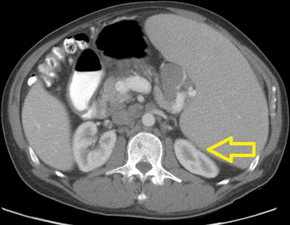

Acute tumor lysis syndrome after proximal splenic artery embolization-CT of abdomen shows splenomegaly with compression of left renal parenchyma arrow

TLS should be suspected in patients with large tumor burden who develop acute kidney failure along with hyperuricemia (> 15 mg/dL) or hyperphosphatemia (> 8 mg/dL). (Most other acute kidney failure occurs with uric acid < 12 mg/dL and phosphate < 6 mg/dL). Acute uric acid nephropathy is associated with little or no urine output. The urinalysis may show uric acid crystals or amorphous urates. The hypersecretion of uric acid can be detected with a high urine uric acid - creatinine ratio > 1.0, compared to a value of 0.6–0.7 for most other causes of acute kidney failure.[citation needed]